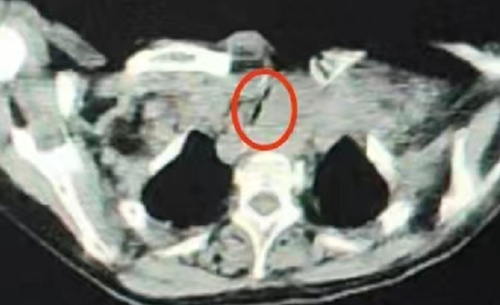

红圈所示为肿瘤,缝隙状为受压的气管

“老人入急诊科时,皮肤湿冷,口唇发绀,呼吸心跳停止,予以胸外心脏按压及经口气管插管、呼吸机辅助通气等系列抢救措施后生命体征恢复平稳。”急诊室接诊医生曾昭介绍,完善胸部CT检查后发现:甲状腺巨大肿瘤导致气管受压变窄(接近闭塞),整个气道被压成了一条缝隙。如果不解决气道梗阻的问题,患者将一直需要依赖气管插管,呼吸机维持通气。